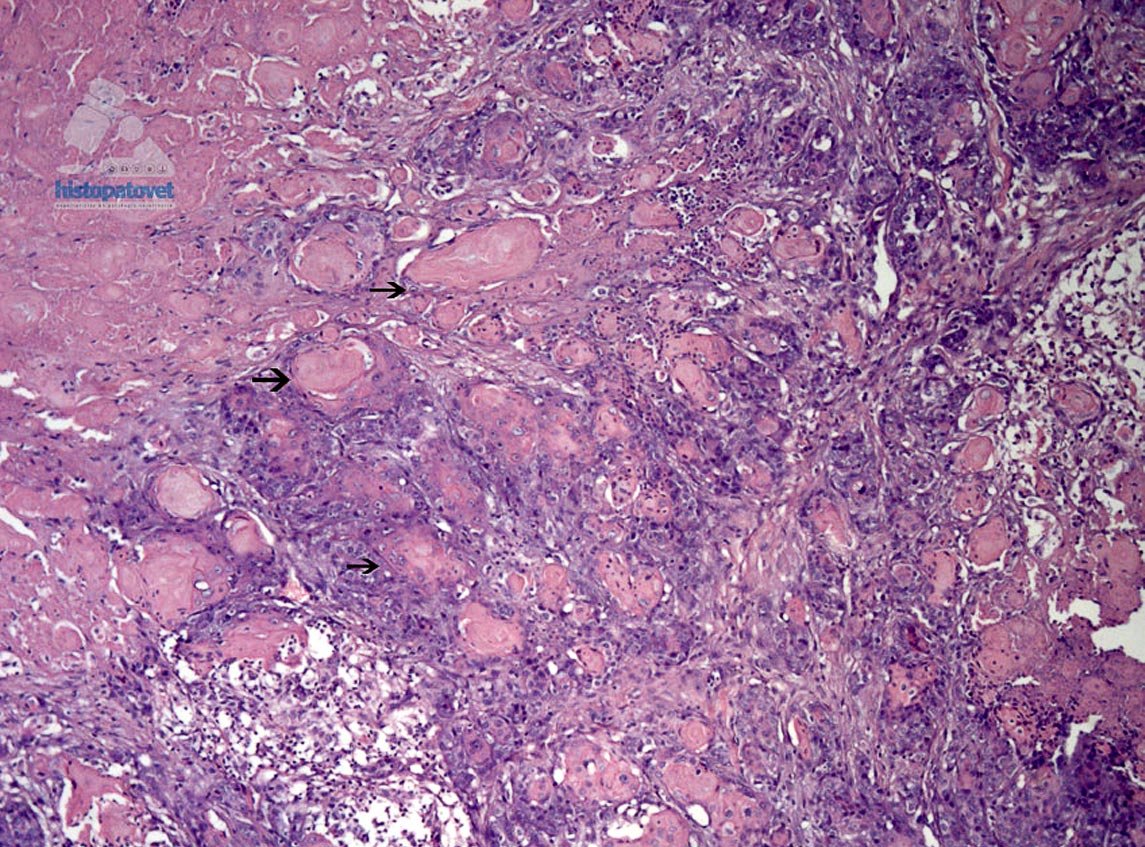

Fig.4. Las flechas indican centros de formación de queratina.El núcleo es redondo-ovalado, pálido, con uno o dos nucléolos. Además, en muchas partes, las células muestran un clara diferenciación a células escamosas( Fig. 5).

Fig.5. Las flechas indican presencia de queratina.